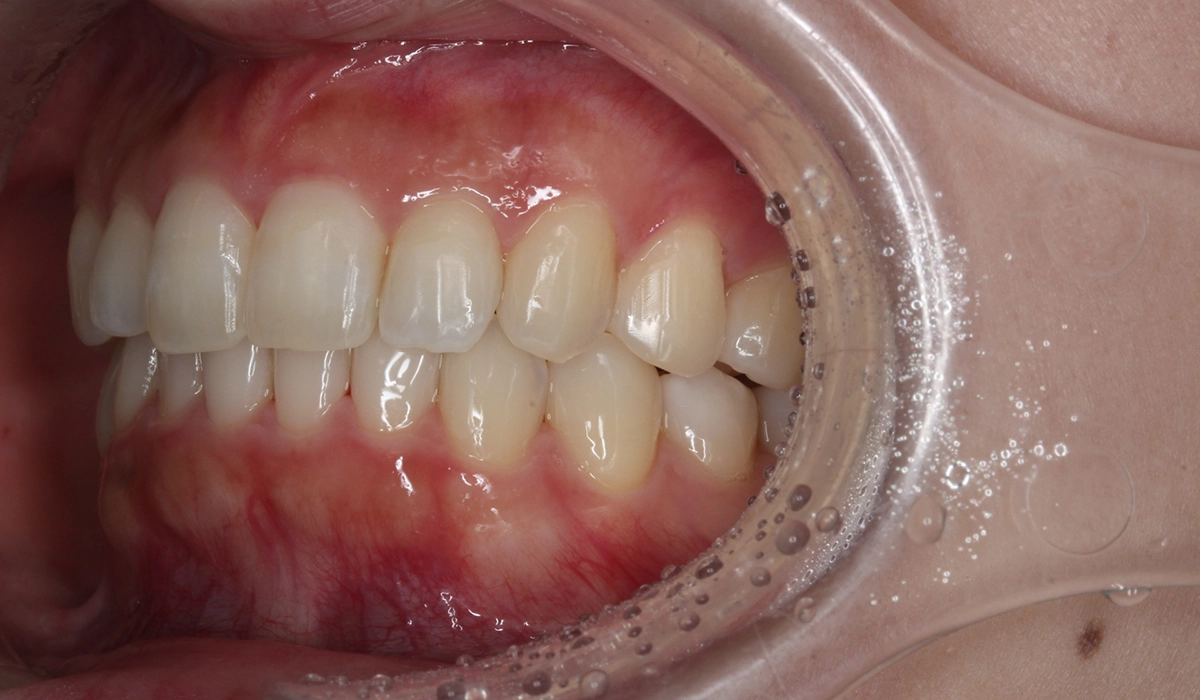

術前:左側

術後:左側